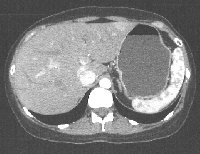

Πρόκειται για ασυμπτωματική γυναίκα ασθενή 35 ετών η οποία, στα πλαίσια διαγνωστικής γυναικολογικής λαπαροσκόπησης, διαπιστώθηκε ότι έφερε πολλαπλές ηπατικές μάζες. Η αξονική τομογραφία που ακολούθησε (εικόνα 1) ανέδειξε εμπλοκή όλων των ηπατικών τμημάτων, με τις περισσότερες βλάβες να βρίσκονται στο αριστερό ημι-ήπαρ. Διενεργήθηκε διαδερμική βιοψία της μεγαλύτερης των βλαβών που έθεσε τη διάγνωση του νευροενδοκρινούς νεοπλάσματος (0-1 μίτωση / 50 HPF και ki67 < 1%, G1). Ο έλεγχος για εύρεση πιθανής πρωτοπαθούς εστίας (MDCT κοιλίας/θώρακος, γαστροσκόπηση, κολονοσκόπηση, ενδοσκόπηση λεπτού εντέρου με καψούλα, octreotide scan) ήταν αρνητικός. Το ογκολογικό συμβούλιο αποφάνθηκε ότι πρόκειται για πρωτοπαθές πολυεστιακό νευροενδοκρινές νεόπλασμα του ήπατος. Το διεγχειρητικό υπερηχογράφημα ανέδειξε συνολικά 22 βλάβες. Για την πλήρη αφαίρεσή τους διενεργήθηκαν αριστερή ηπατεκτομή (εικόνα 2), πολλαπλές (Χ10) άτυπες μικρές δεξιές εκτομές (εικόνα 3), καθώς και μία άτυπη εκτομή του τμήματος 1 μεταξύ της πυλαίας και της κάτω κοίλης φλέβας (εικόνα 4). Το παρασκεύασμα δεικνύεται στην εικόνα 5. Η τελική παθολογοανατομική εκτίμηση του επιβεβαίωσε τα ευρήματα της πρώτηε (εικόνα 6). Η ασθενής έλαβε εξιτήριο την 7η μετεγχειρητική ημέρα. Τέθηκε σε μηνιαία αγωγή με octreotide acetate. Εξακολουθεί να είναι ελεύθερη νόσου.